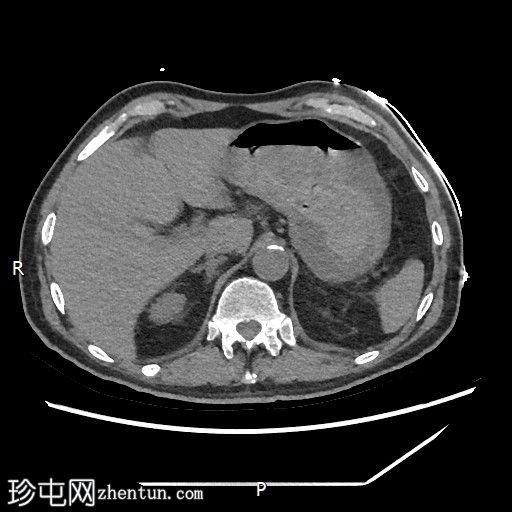

CT

轴位

平扫

1.jpg

轴位增强扫描

动脉期

2.jpg

门静脉期

3.jpg

胃内出血

造影剂外渗提示十二指肠第二段活动性出血

6.jpeg

十二指肠第三段造影剂积聚

活动性出血

7.jpeg

底不张

CT血管造影对检测活动性消化道出血具有较高的敏感性。